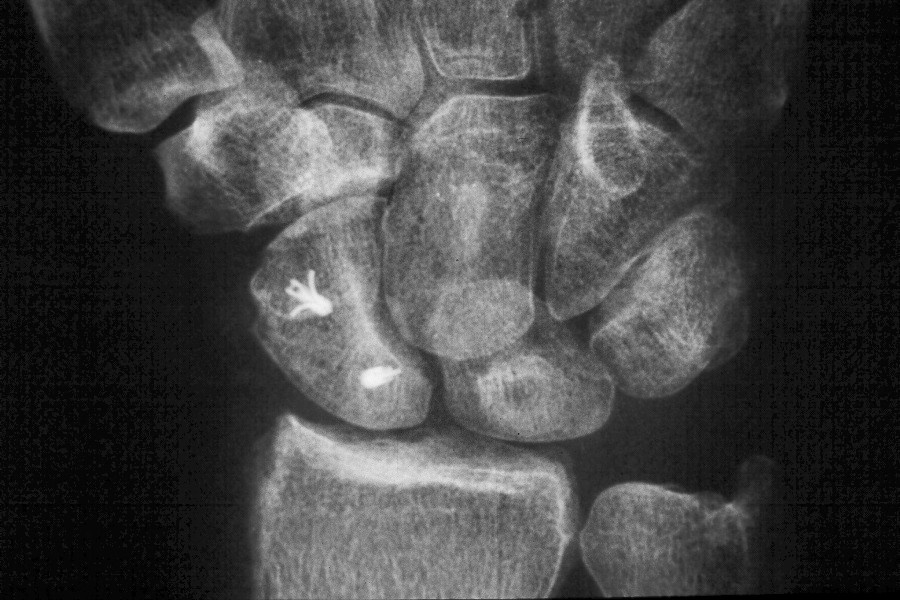

Scapholunate pins and bone anchors - intraoperative fluoroscopy.

Click for larger image